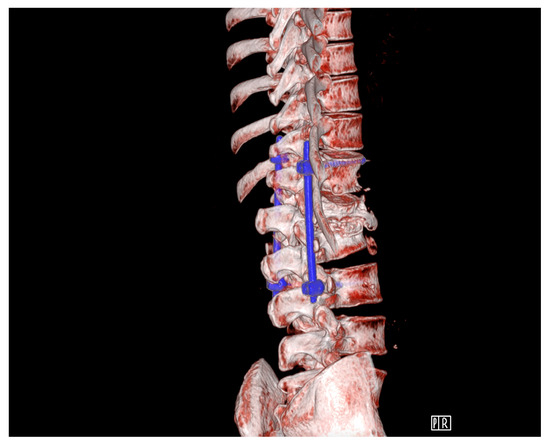

Patient Background: A 35-year-old male, known to be HIV-positive, was diagnosed due to dull pain in the thoracic spine. MRI diagnostics revealed a pathological fracture at the L1 level with a mass expanding towards the spinal canal, causing critical compression of the conus medullaris. Despite the dramatic radiological appearance, the patient exhibited only pain symptoms. A decision was made to perform stabilization using a percutaneous technique with biopsy of the lesion. During the procedure, it was determined that the lesion was fluid-filled, leading to a decision to expand the scope of the operation to include left-sided facetectomy of TH12/L1 and removal of the dense purulent content filling the spinal canal.

Diagnostic Evaluation: Cultures taken were sterile, and the patient was empirically treated with antibiotics until inflammatory markers decreased. He was discharged in good condition without pain. Six months later, the surgical site re-opened with purulent discharge seeping out. A new culture was taken, which returned sterile. Laboratory tests showed an increase in inflammatory markers, and the patient periodically experienced fever. CT scans showed the stabilization was in the correct position but without signs of bone fusion, and MR images showed inflammatory masses within the spinal canal (Figure 9 and Figure 10).

Figure 9. Pre-operative transpedicular stabilization Th12-L3, CT 3D reconstruction.